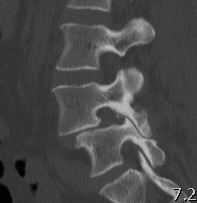

CT scan

Technique

- reverse gantry

Indication

- perform instead of obliques

- oblique x-rays have high radiation dose with little extra information compared with CT

Spondylolysis

Definition

- radiolucent defect of pars

Types

- acute - narrow gap & irregular edges

- pars elongated & thinned

- chronic - wide gap with smooth sclerotic edges